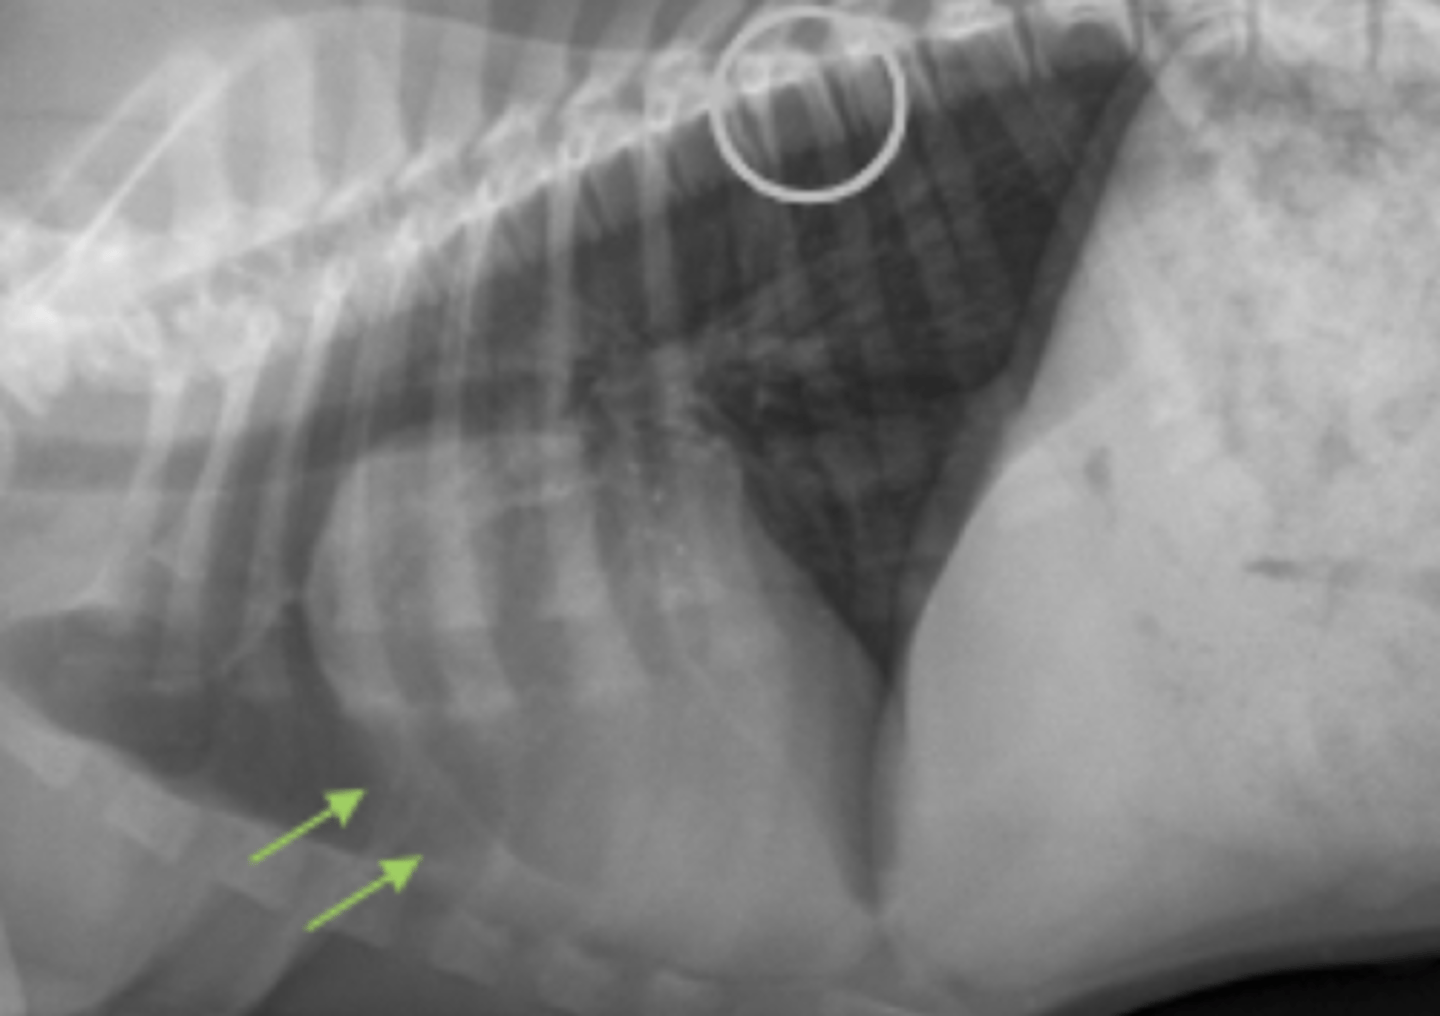

megaesófago

patología:

megaesófago, por cuerpo extraño

neumonía por aspiración por

la parenquíma pulmonar, por riesgo de neumonía por aspiración

si vemos megaesófago en una radiografía, es importante evaluar: